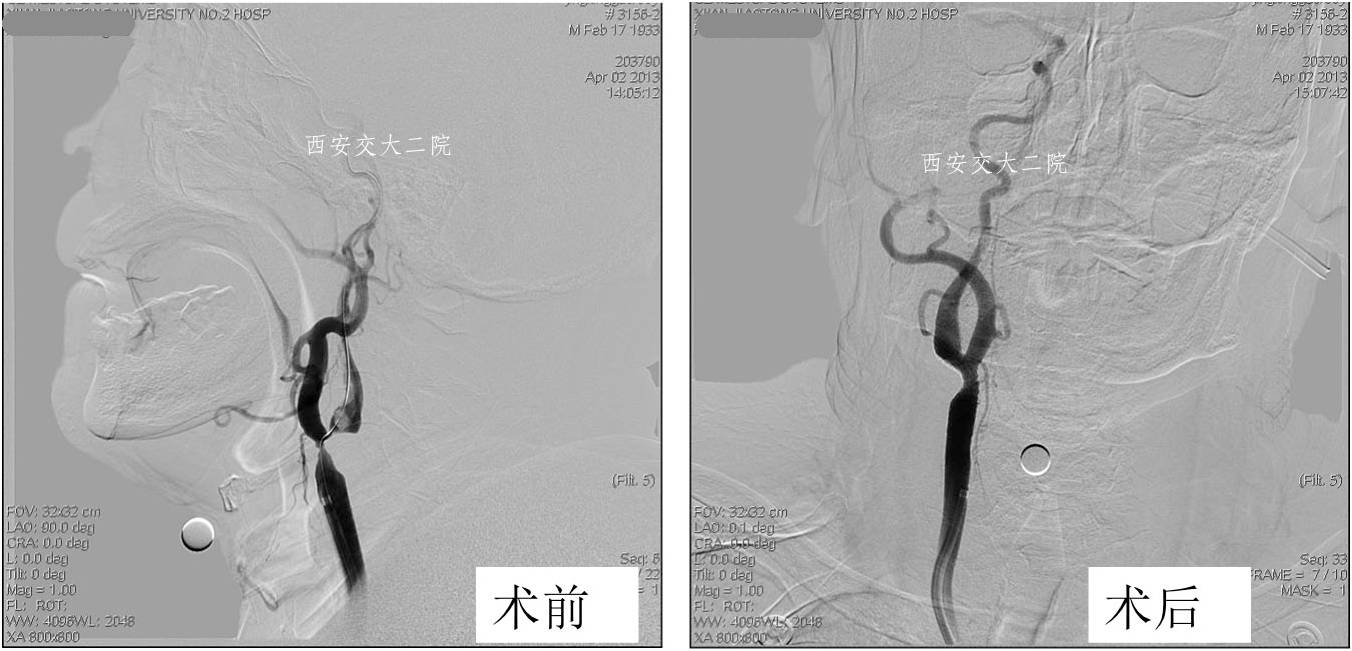

Case 4 颈内动脉颅内段闭塞再通术

》女,57岁;

》左侧肢体无力1月于2014.1.8入院;

》诊断:脑梗死(右侧半卵圆中心)。

术前脑CT

术后患者病情逐渐好转。

术后3月自动停药,1年后再发右侧颈内动脉供血区脑梗,复查DSA见再通支架处血管再次闭塞。